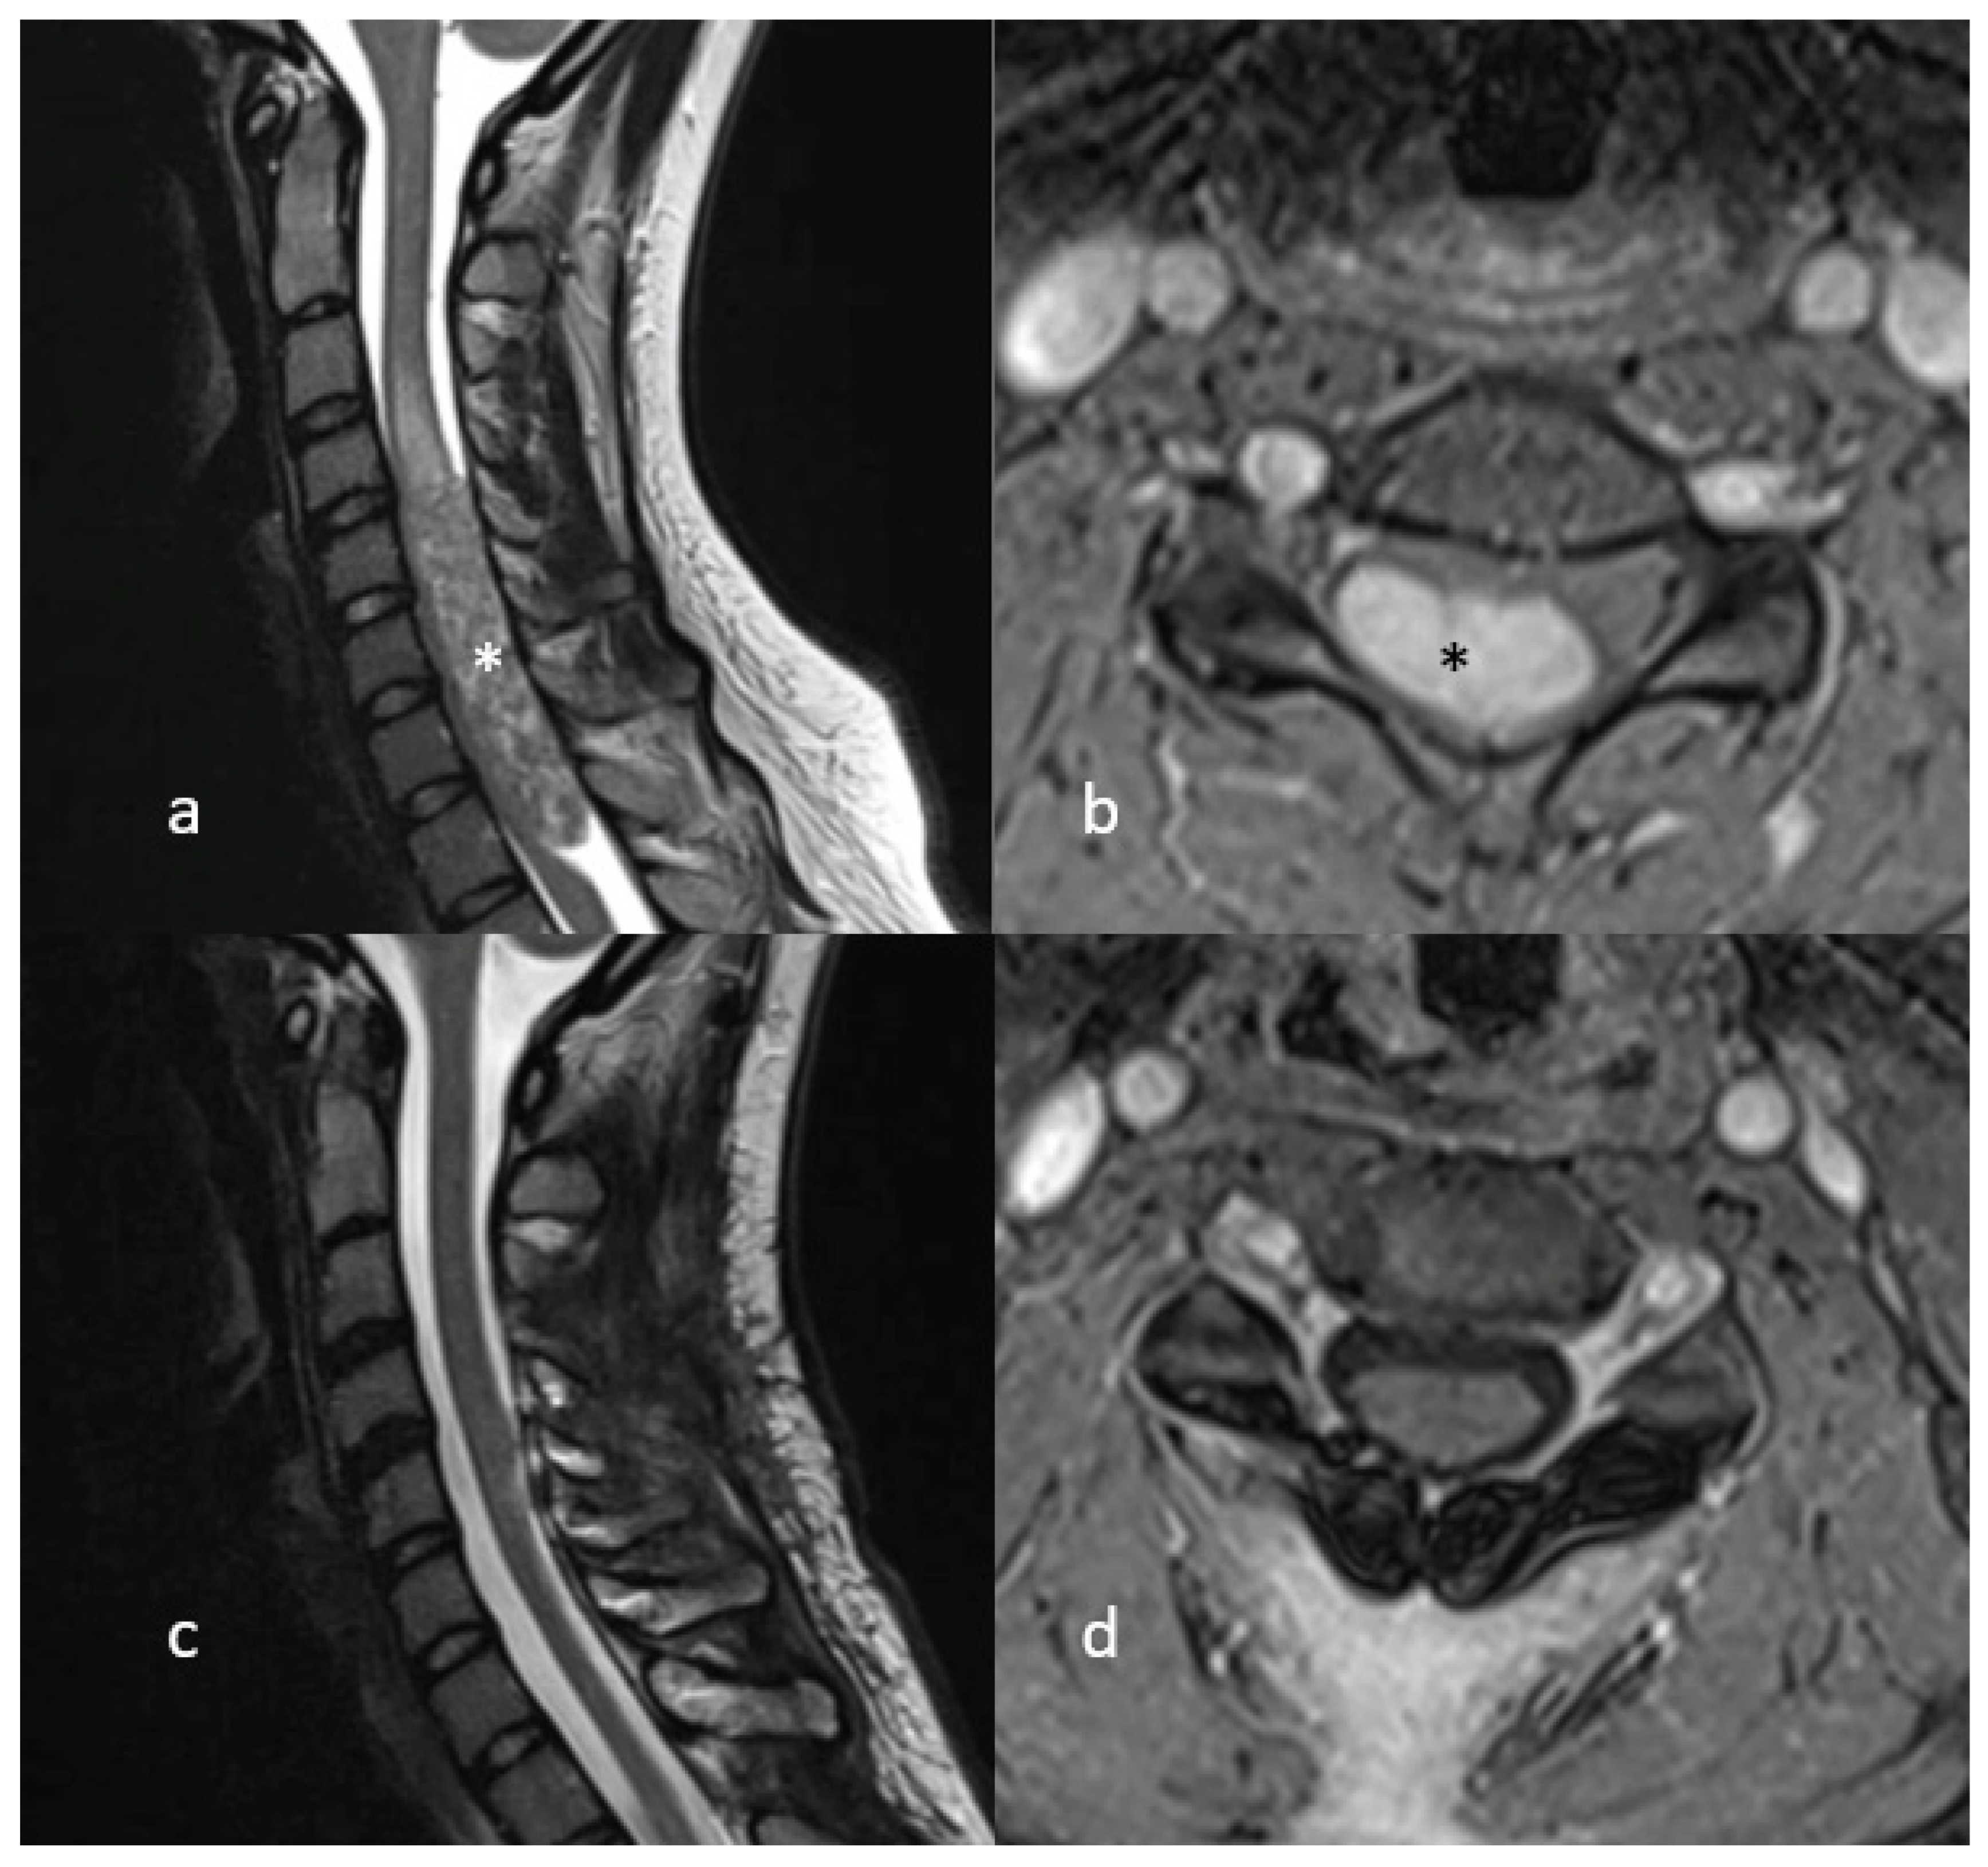

4. Illustrative Case